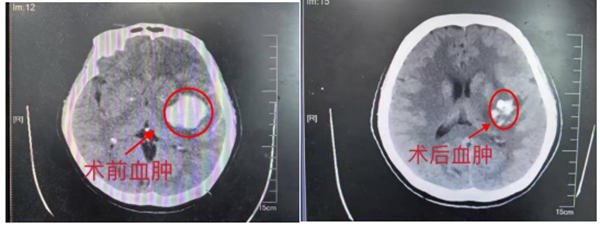

52岁的王女士因“突发右侧肢体瘫伴意识障碍1小时”紧急入院,经CT检查确诊为左侧基底节区出血,出血量约25ml,处于浅昏迷状态,右侧肢体肌力为0级,神经功能障碍突出。“患者出血量属中小型、年龄相对较轻,但病情进展快,传统开颅手术创伤大,保守治疗血肿吸收慢,可能错过最佳恢复时机。”该院神经外科张东强主任团队综合评估后,决定采用AI辅助下的精准微创手术方案。

整个手术在局部麻醉下完成,医生仅在患者颅骨上钻一个2-3毫米的微孔,便将引流导管精准置入血肿腔,术后通过注入溶栓药物实现血肿持续温和引流。复查CT显示,患者颅内血肿基本清除,不仅手术创伤极小,恢复速度也远超传统治疗。术后当即恢复语言能力,第二天右侧肢体功能明显改善,有效降低了并发症风险和致残率。